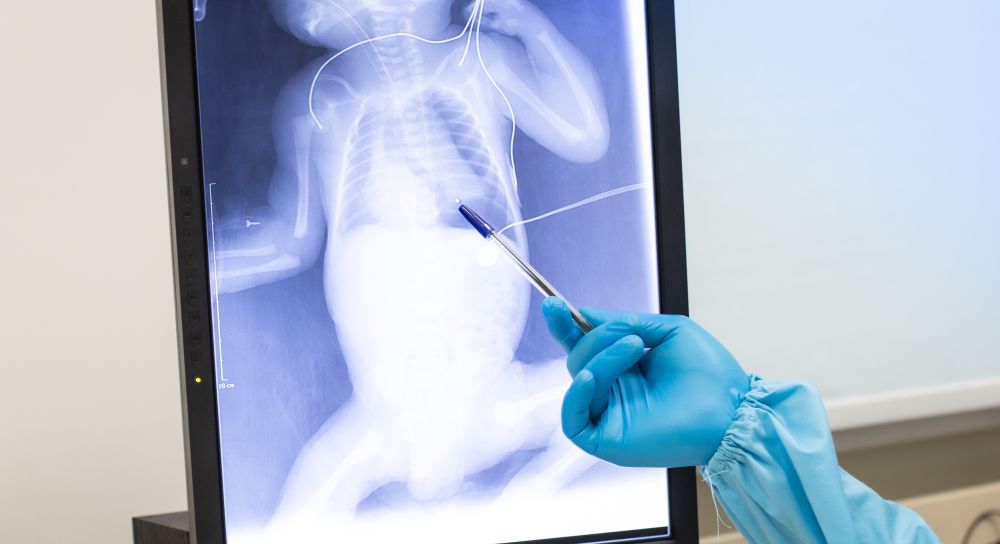

Реанимационно-консультативная неонатальная бригада врачей доставила в отделение реанимации и интенсивной терапии новорожденных Сергиево-Посадского роддома ребёнка в тяжёлом состоянии. Мальчик родился на 30 неделе беременности с подтвержденной коронавирусной инфекцией. В течение первых суток жизни на фоне пневмонии и коронавируса у малыша развился пневмоторакс – это наличие воздуха в плевральной полости между грудной стенкой и лёгким. Кроме того, анамнез был отягощен анемией.

«При таком тяжёлом развитии болезни был крайне высокий риск неблагоприятного исхода. Пнемоторакс мы успешно дренировали, далее предстояло вылечить пневмонию. У ребёнка также была анемия, пришлось делать переливания крови. На третьи сутки развилось кровотечение, в связи с этим потребовалось проведение плазмотрансфузии для купирования кровотечения. Первые трое суток, когда развились такие тяжёлые патологии, были самыми сложными. Ребёнок провёл в отделении 17 дней. Когда состояние пошло на улучшение, с отрицательными мазками новорождённого перевели в другое учреждение на дальнейшее долечивание – сейчас он в удовлетворительном состоянии выписан домой», — рассказал заведующий отделением реанимации и интенсивной терапии новорожденных Сергиево-Посадской районной больницы Кирилл Сыриков.